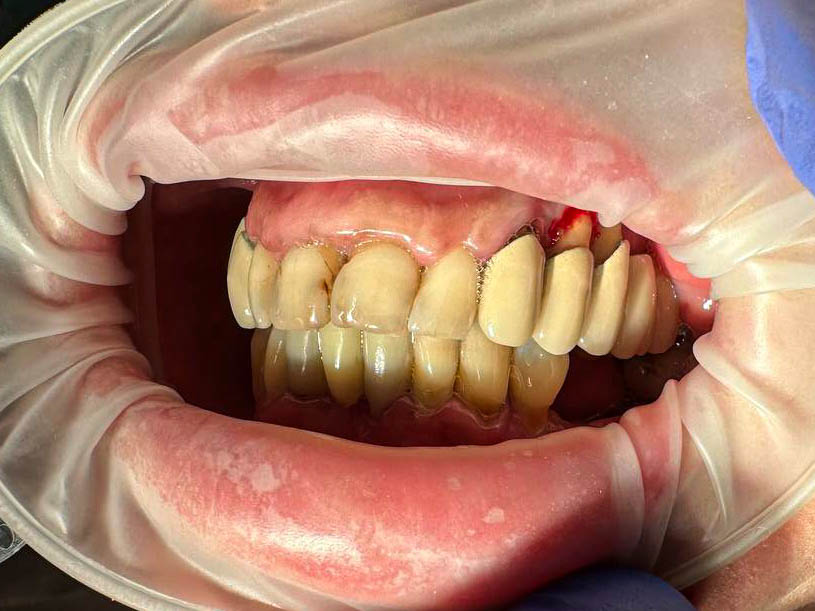

Ситуация до лечения

Пациент обратился с жалобами на эстетические недостатки.

пациент до имплантации